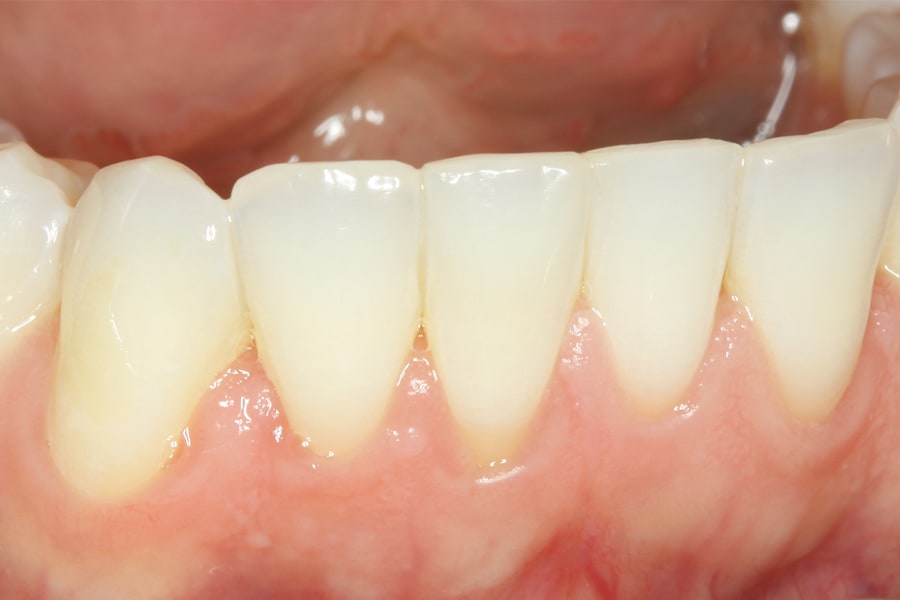

There are, however, some unfavorable long-term ramifications of this design. Due to the nature of stainless steel, which has memory and over time will partially return to its original shape, these twisted lingual retainers may "unwind" or uncoil and exert unintended forces on the teeth to which they are bonded (Figure 5 and Figure 6, Figure 8 through Figure 11, Figure 14 through Figure 16). This leads to excessive labial or lingual root torquing movements, often resulting in highly undesirable recessions, dehiscences, and fenestrations. Because it may take years for this occurrence to manifest, the orthodontist (who usually places the retainer) is typically both unaware of the situation, as he or she does not customarily follow patients for such long-term periods, and free of blame. The periodontal implications of this outcome can be highly detrimental, as seen in the cases presented herein.

Obviously, more suitable and reliable fixed lingual retention designs are needed, and, fortunately, many are available. As described above, the twisted chairside fabricated design can be unreliable. A well-suited alternative is a passive braided design as shown in Figure 2 (Ortho FlexTech® stainless steel, Reliance Orthodontics, relianceorthodontics.com). The braided design does not uncoil over time. The lingual retainer is placed in passive fashion after being cut to the proper length from a spool and bonded to the appropriate teeth. This relatively inexpensive alternative is fabricated chairside with no laboratory intervention or special preparation required. One potential downside is that it is a relatively bulky option.